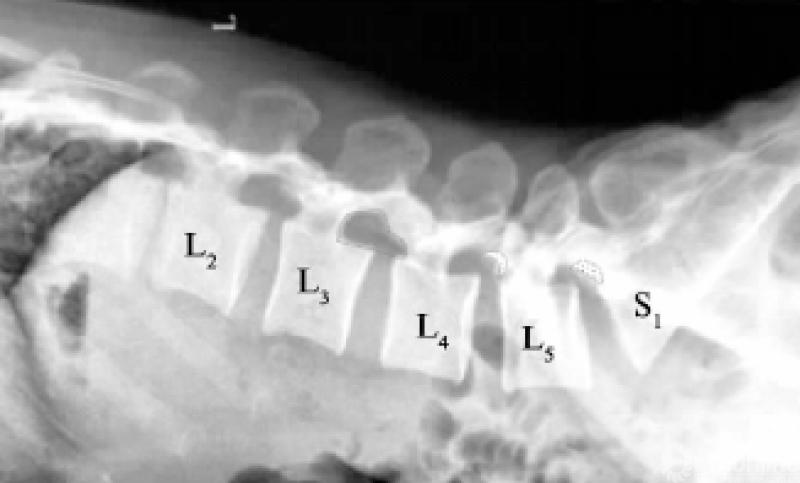

腰椎椎间孔形态与Kambin's三角空间密切相关,而Kambin's三角空间大,工作通道置管时则相对容易,安全系数高,反之则易损伤出口神经根。腰椎椎间孔呈上宽下窄的耳朵状,一般情况下孔的高度在腰椎各节段中相差不大,约20mm[25];L2/3椎间孔的上下径最大,越往下越小(见图5)。而孔的宽度或者厚度,一般由L1/2至L5S1递增,在L5S1中可达约19.8mm[25],这与腰关节突关节面由矢状位向冠状位变化有关。

有研究指出,冠状面上神经根分出硬脊膜时的倾斜角度,由T11根至L5根位置逐渐变小,到L5时约25°[26],腰椎节段神经根出行角度的变化意味着Kambin's三角空间的多样性。杨晋才等[27]指出,出口神经根与上关节突之间存在呈梯形的“骨-神经间隙”,适当行关节突成形可避免损伤出口神经根。笔者认为不同节段的腰椎间盘突出,由于腰椎椎间孔形态的不同,穿刺方向及是否行关节突成形应有区别。

L3/4以上节段椎间孔相对宽大,如图中虚线“耳朵状”;L4/5及L5S1节段椎间孔相对狭小,“半月形”轮廓为切除上关节突范围示意图

图5 34岁男性腰椎侧位X线片